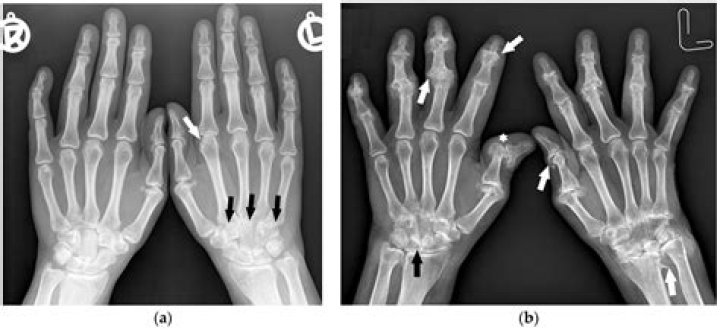

Radiographs show typical findings such as soft-tissue swelling, marginal erosions, periarticular osteopenia, joint space narrowing, and joint subluxation. Besides bone alterations, this imaging modality is unable to display synovitis at an early stage.